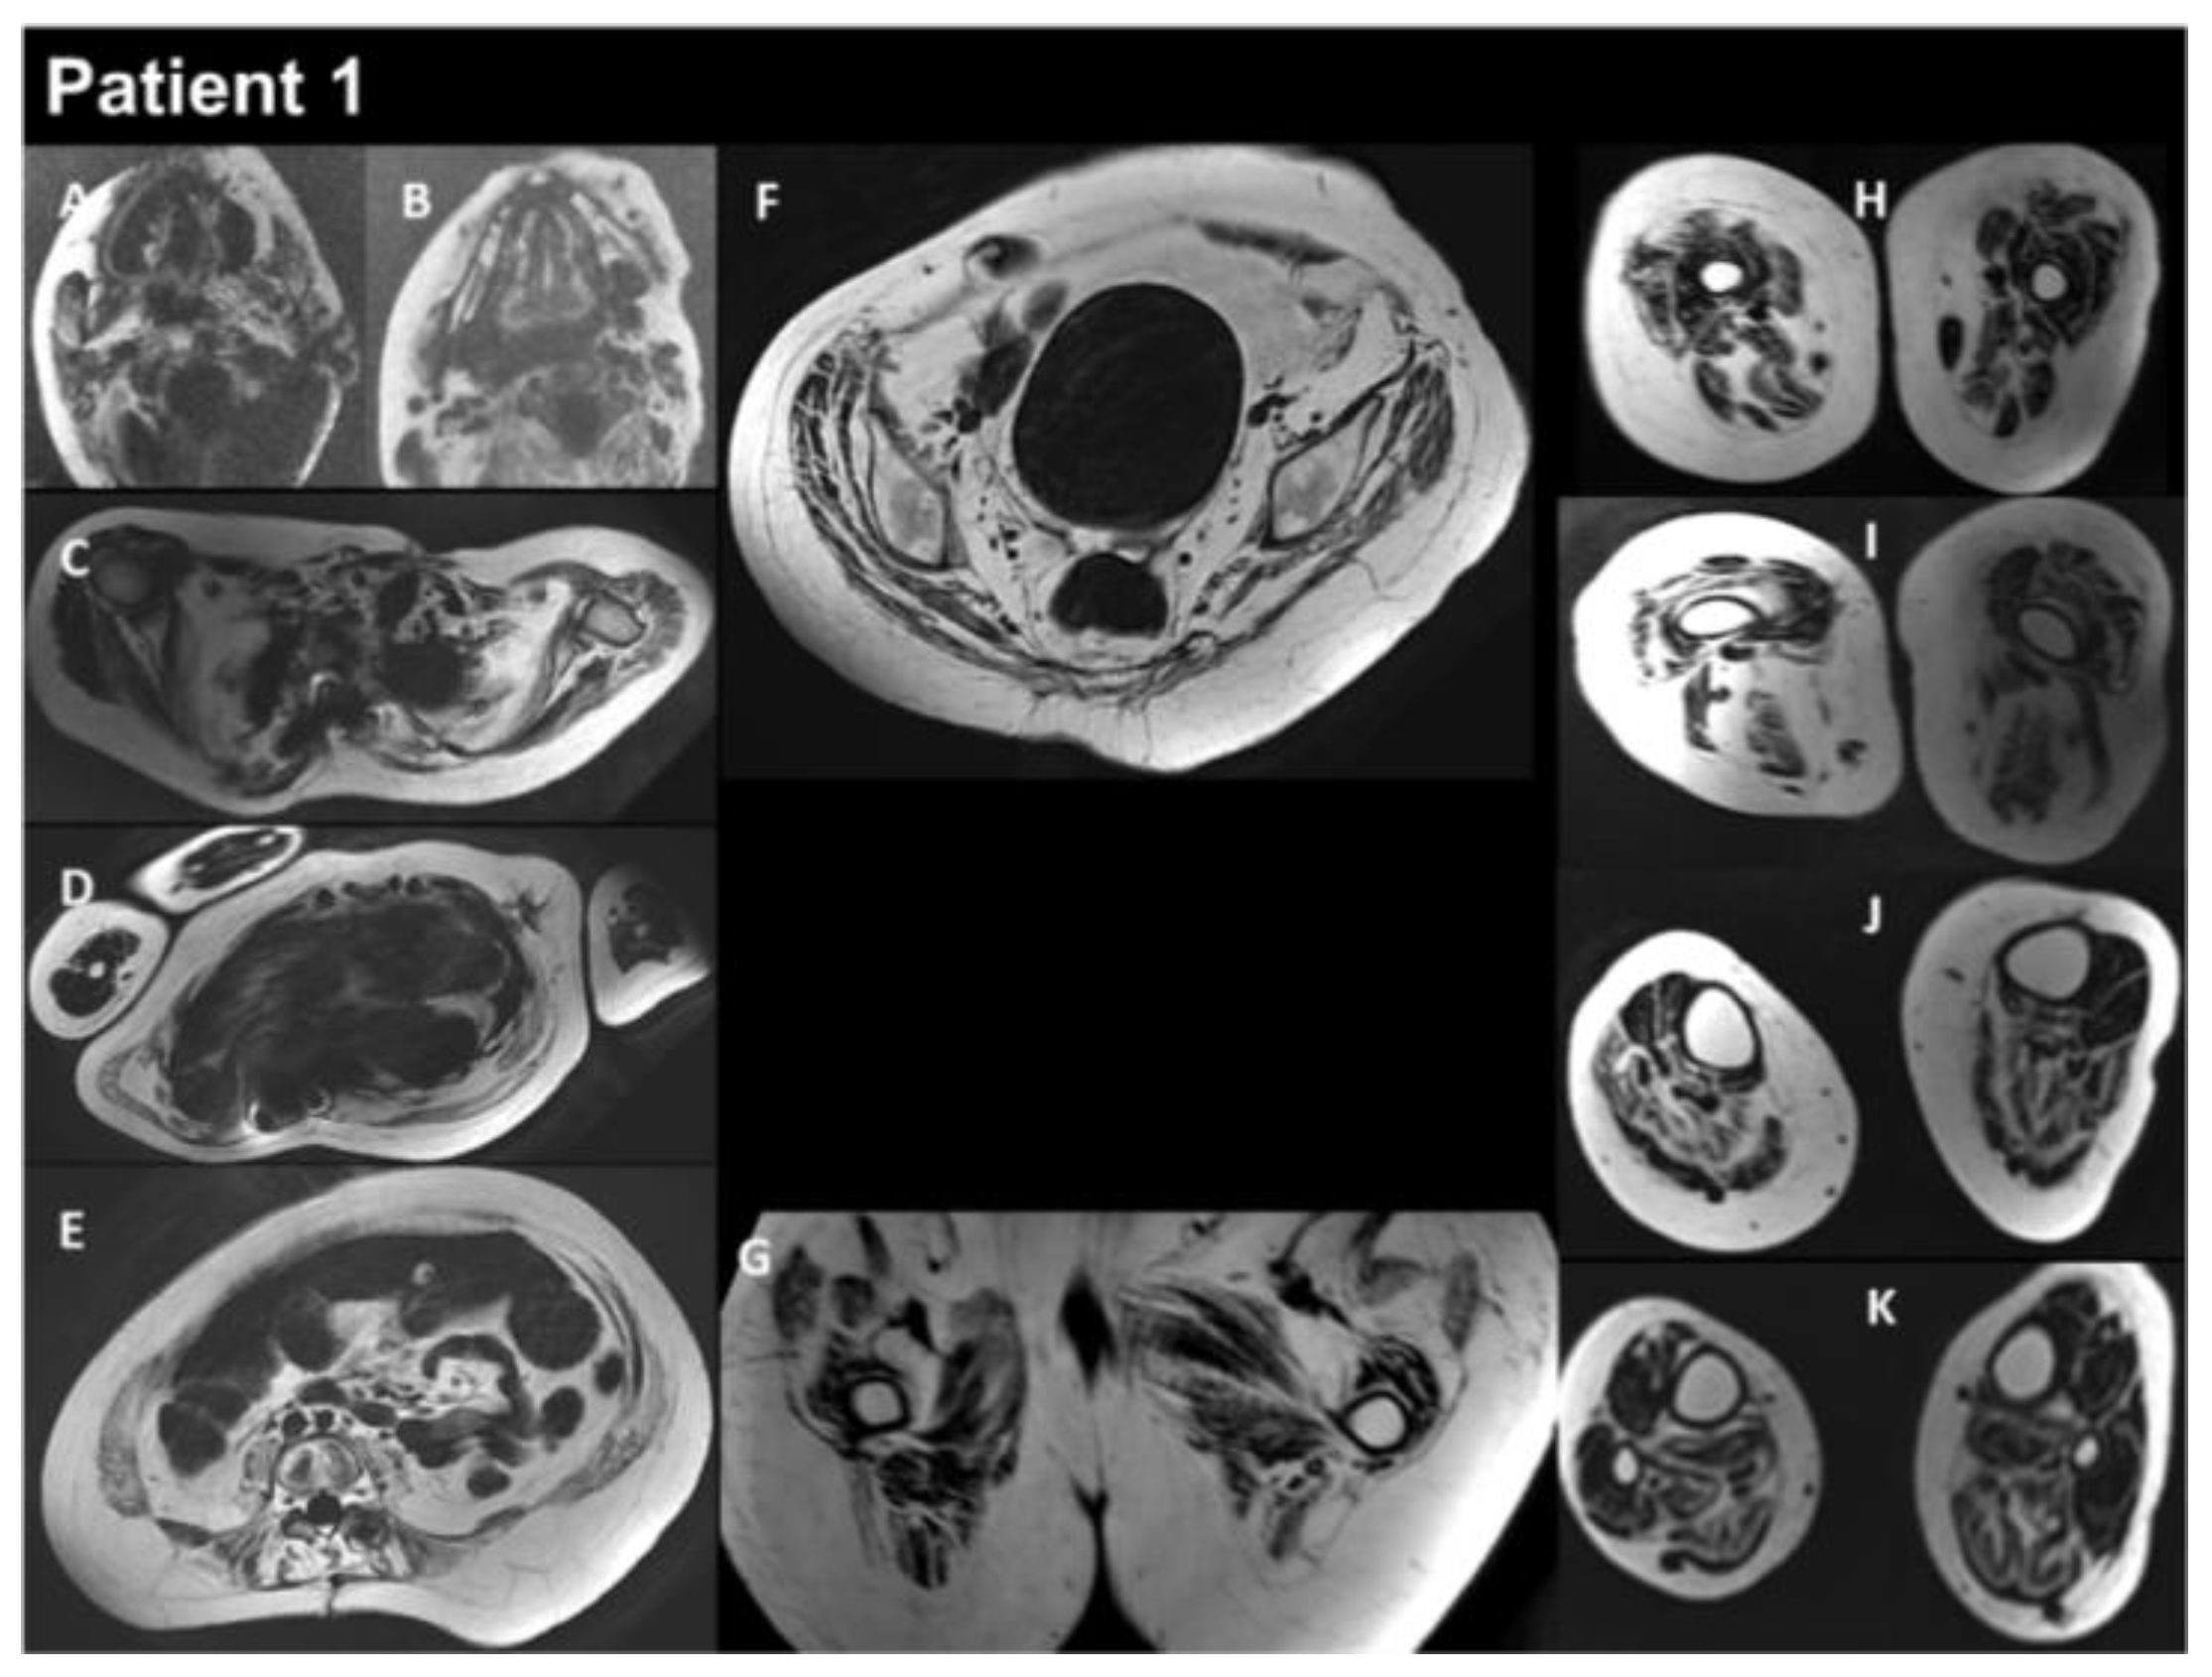

3.1. Patients’ Characteristics

| THIS STUDY | P1 | M | heteroz., de novo | RCM + myopathy | Birth | 13 y | Global | Yes | Yes | Myopathic | Normal | RCM | Restrictive respiratory syndrome | Alive at 17 y | Yes |

| P2 | M | heteroz. | HCM + myopathy | 2 y | 39 y | Global | - | Yes | - | Increased | HCM | Restrictive respiratory syndrome | Alive at 43 y | Yes | |

| P3 | F | heteroz. | HCM + myopathy | 3–4 y | 29 y | Axial and proximal | - | Yes | - | Increased | HCM | Restrictive respiratory syndrome | Alive at 34 y | Yes | |